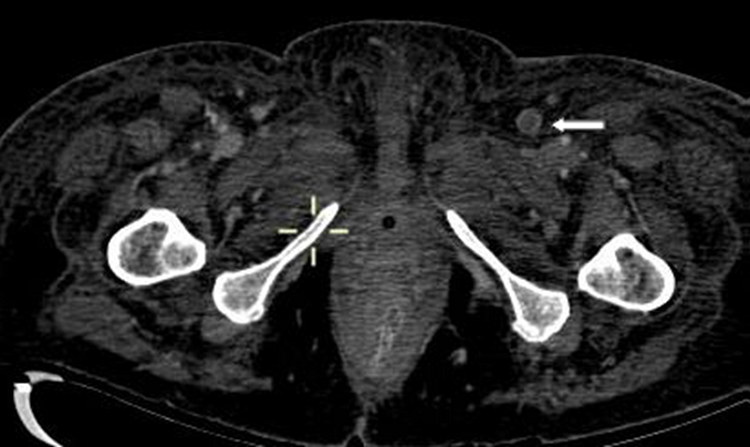

Todos los pacientes de la serie tenían hipoxia y aumento de las cifras de Dímero D con normalización en la cifra de otros parámetros típicamente alterados en esta enfermedad. De los ocho pacientes con TEP solo en dos había afectación múltiple y en ramas principales y lobares (Figura 1). En uno de los dos casos días después se confirmó la existencia de una extensa trombosis de las venas iliacas y femoral derecha como causa del TEP (Figura 2). En los otros seis casos el trombo era único y en ramas de pequeño calibre (Figura 3). En uno de los pacientes el trombo afectaba a la vena pulmonar superior izqda (Figura 4).